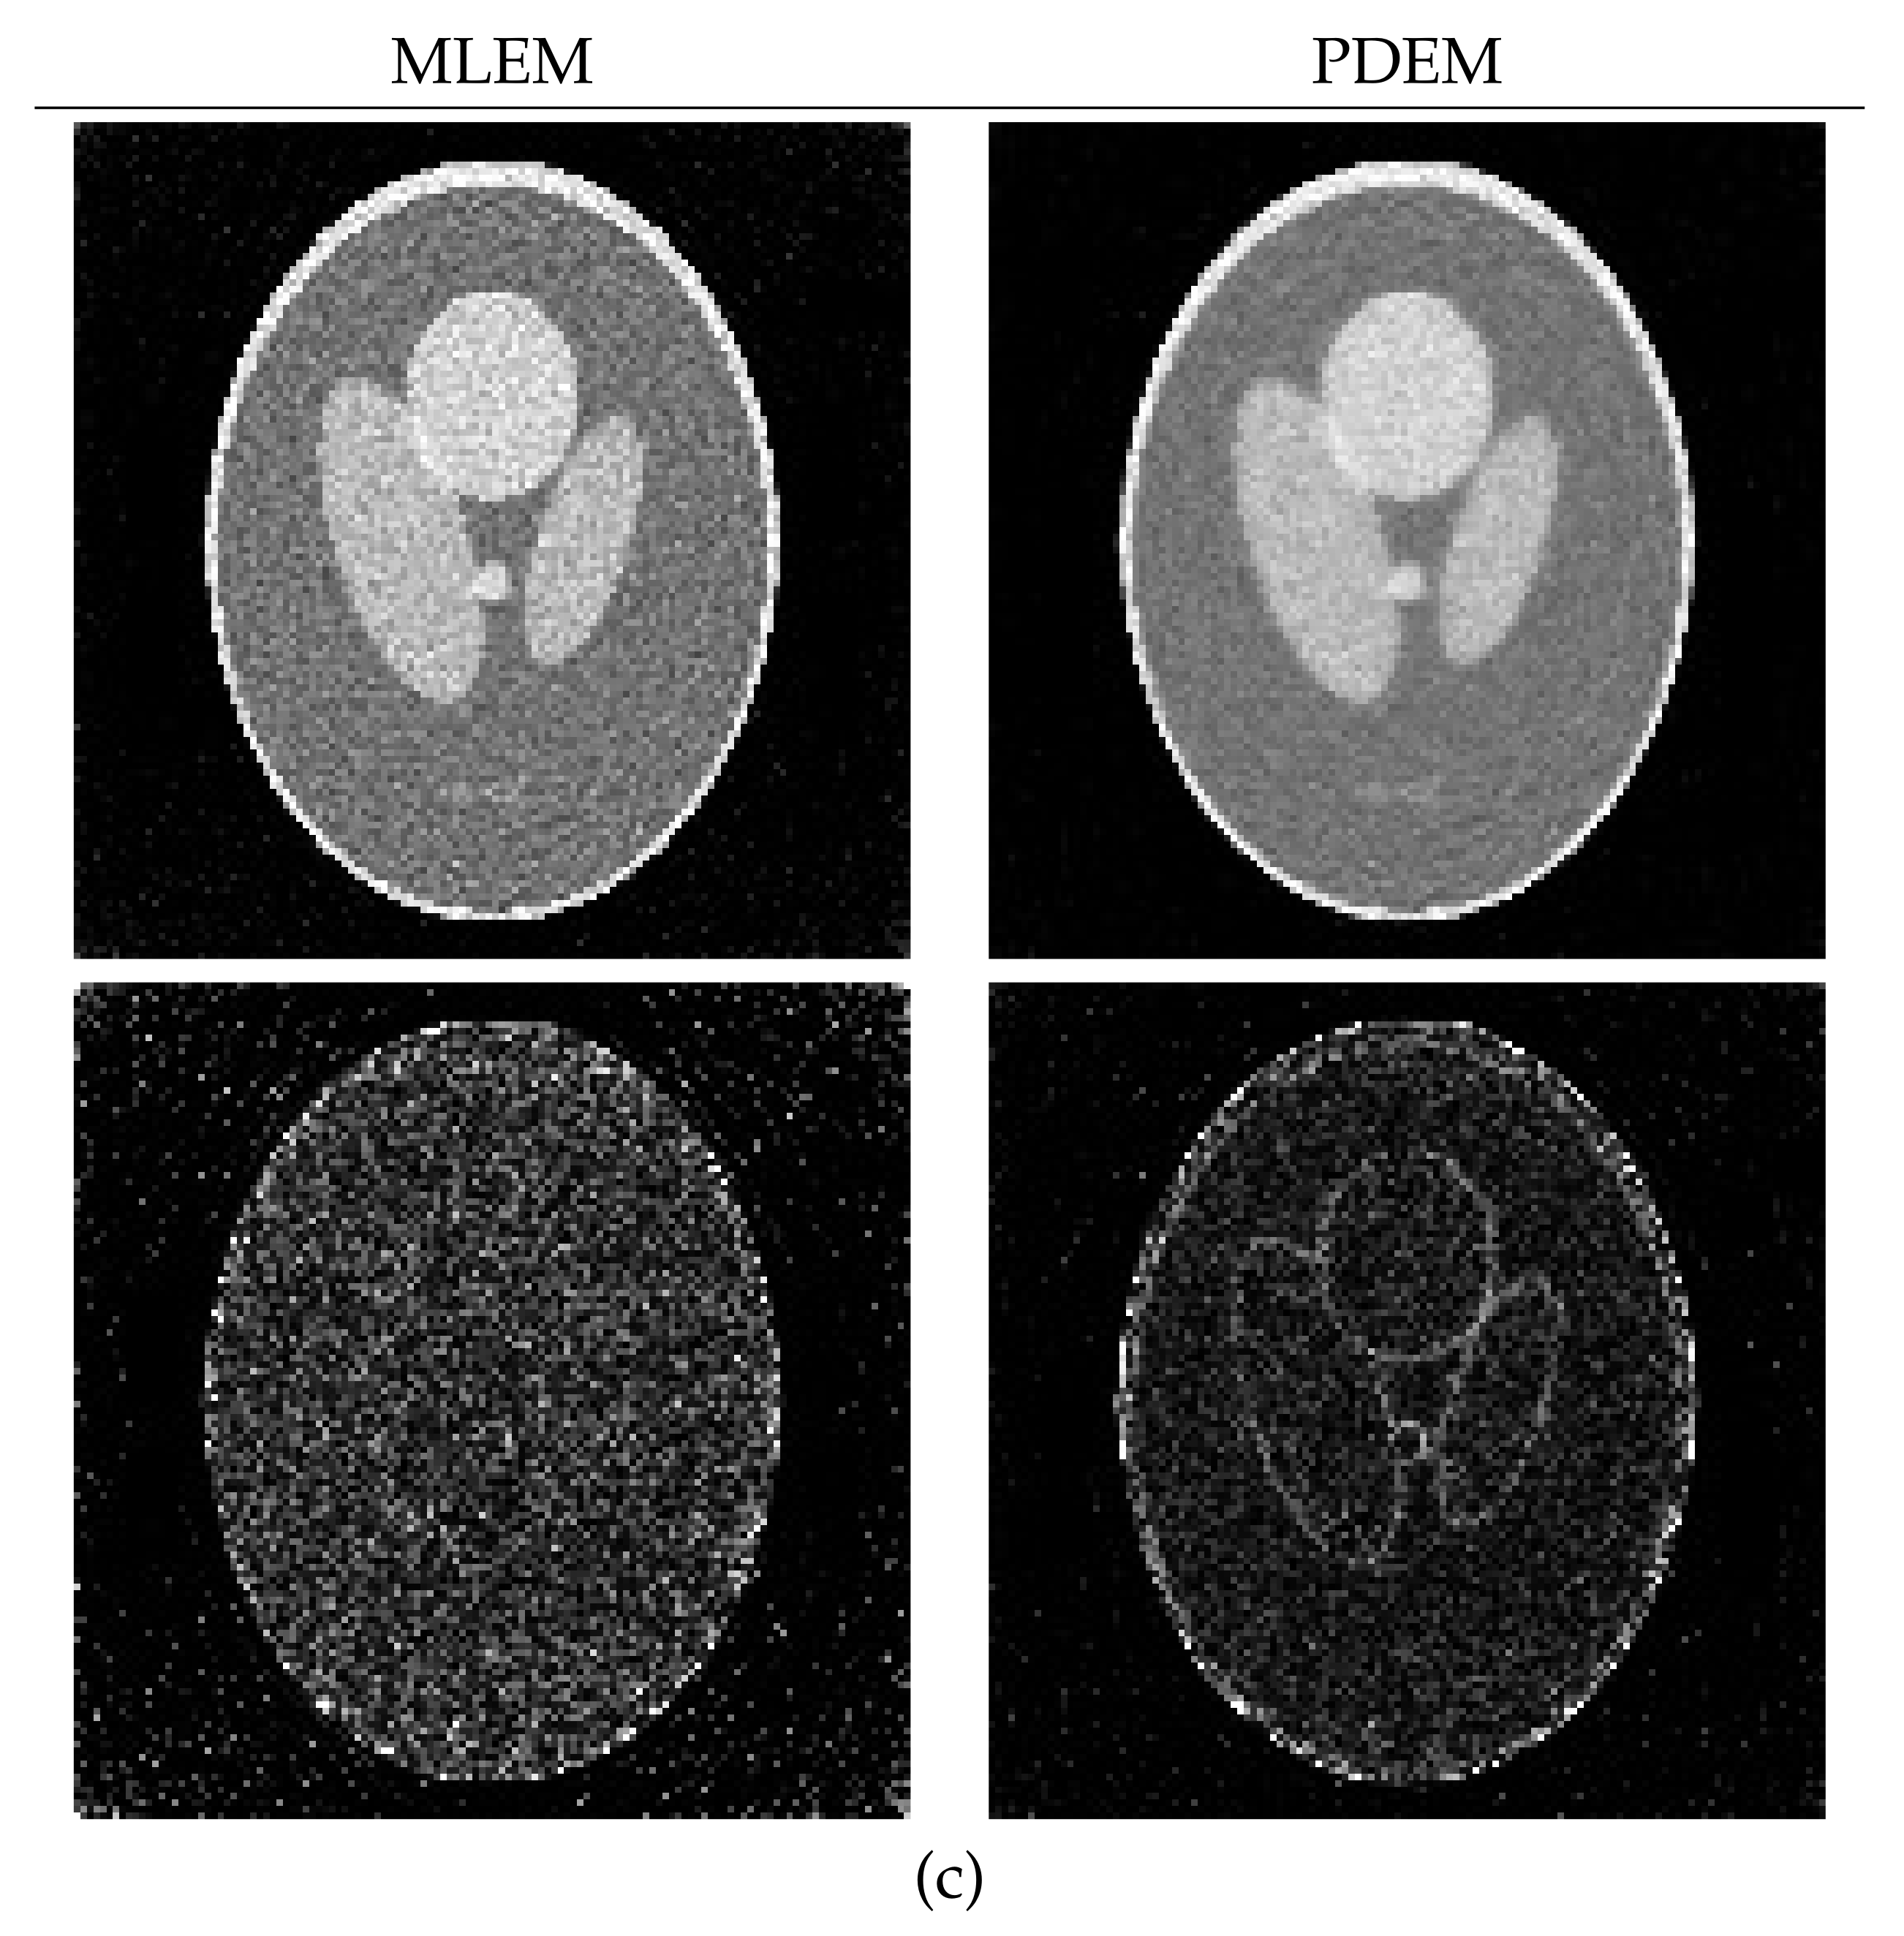

4.1. Reconstruction Using Numerical Phantom

4.2. Reconstruction Using Physical Phantom